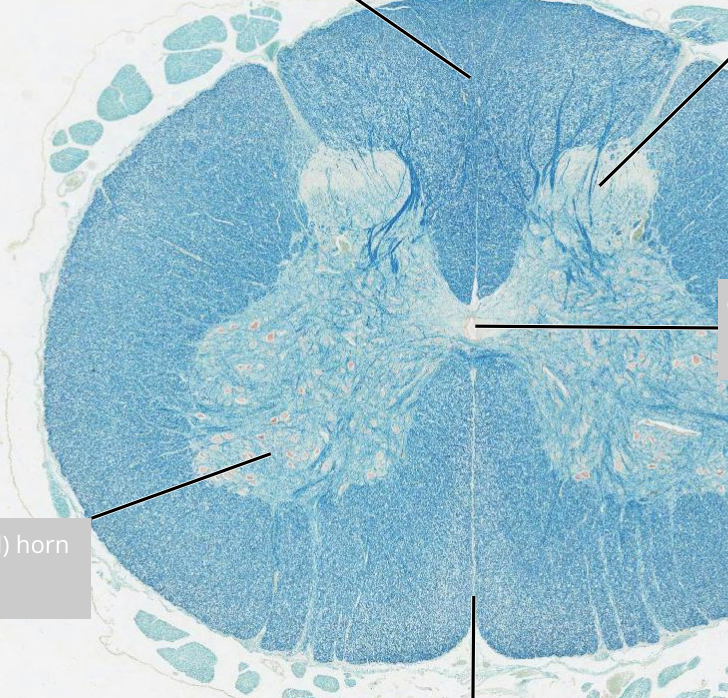

<p>label spinal cord</p>

label spinal cord

knowt flashcard image